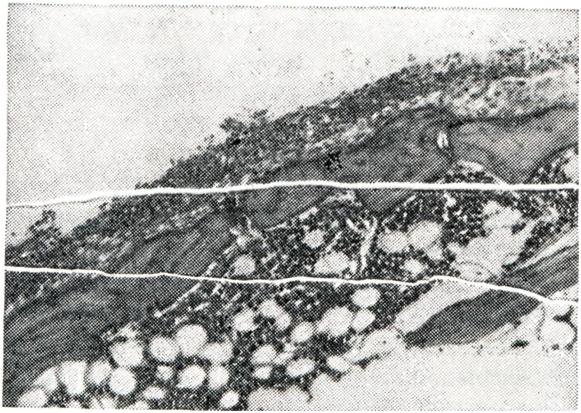

При микроскопии суставного хряща наблюдается его разволокнение, очаги некроза с образованием дефектов хрящевого покрытия и узурированием кости. Дефекты хряща замещаются грануляционной тканью, наползающей на суставную поверхность в виде различной толщины пленки (паннуса) — паннозный артрит. (рис. 2 и 3).

Рис. 3. | ||